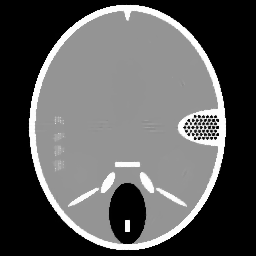

Figure 1. Phantoms for tests. (a) Head phantom used for simulation [24], (b) gel phantom used for real X-ray scan.

For the experiments, we test our method on a simulated head phantom from [24] and a real gel phantom shown in Figure 1. Here, we consider a 2D CT scenario. The detector has full coverage of the object at any projection angle, and a constant angular spacing of the rays is set in the interval of [0,π]0𝜋[0,\pi].